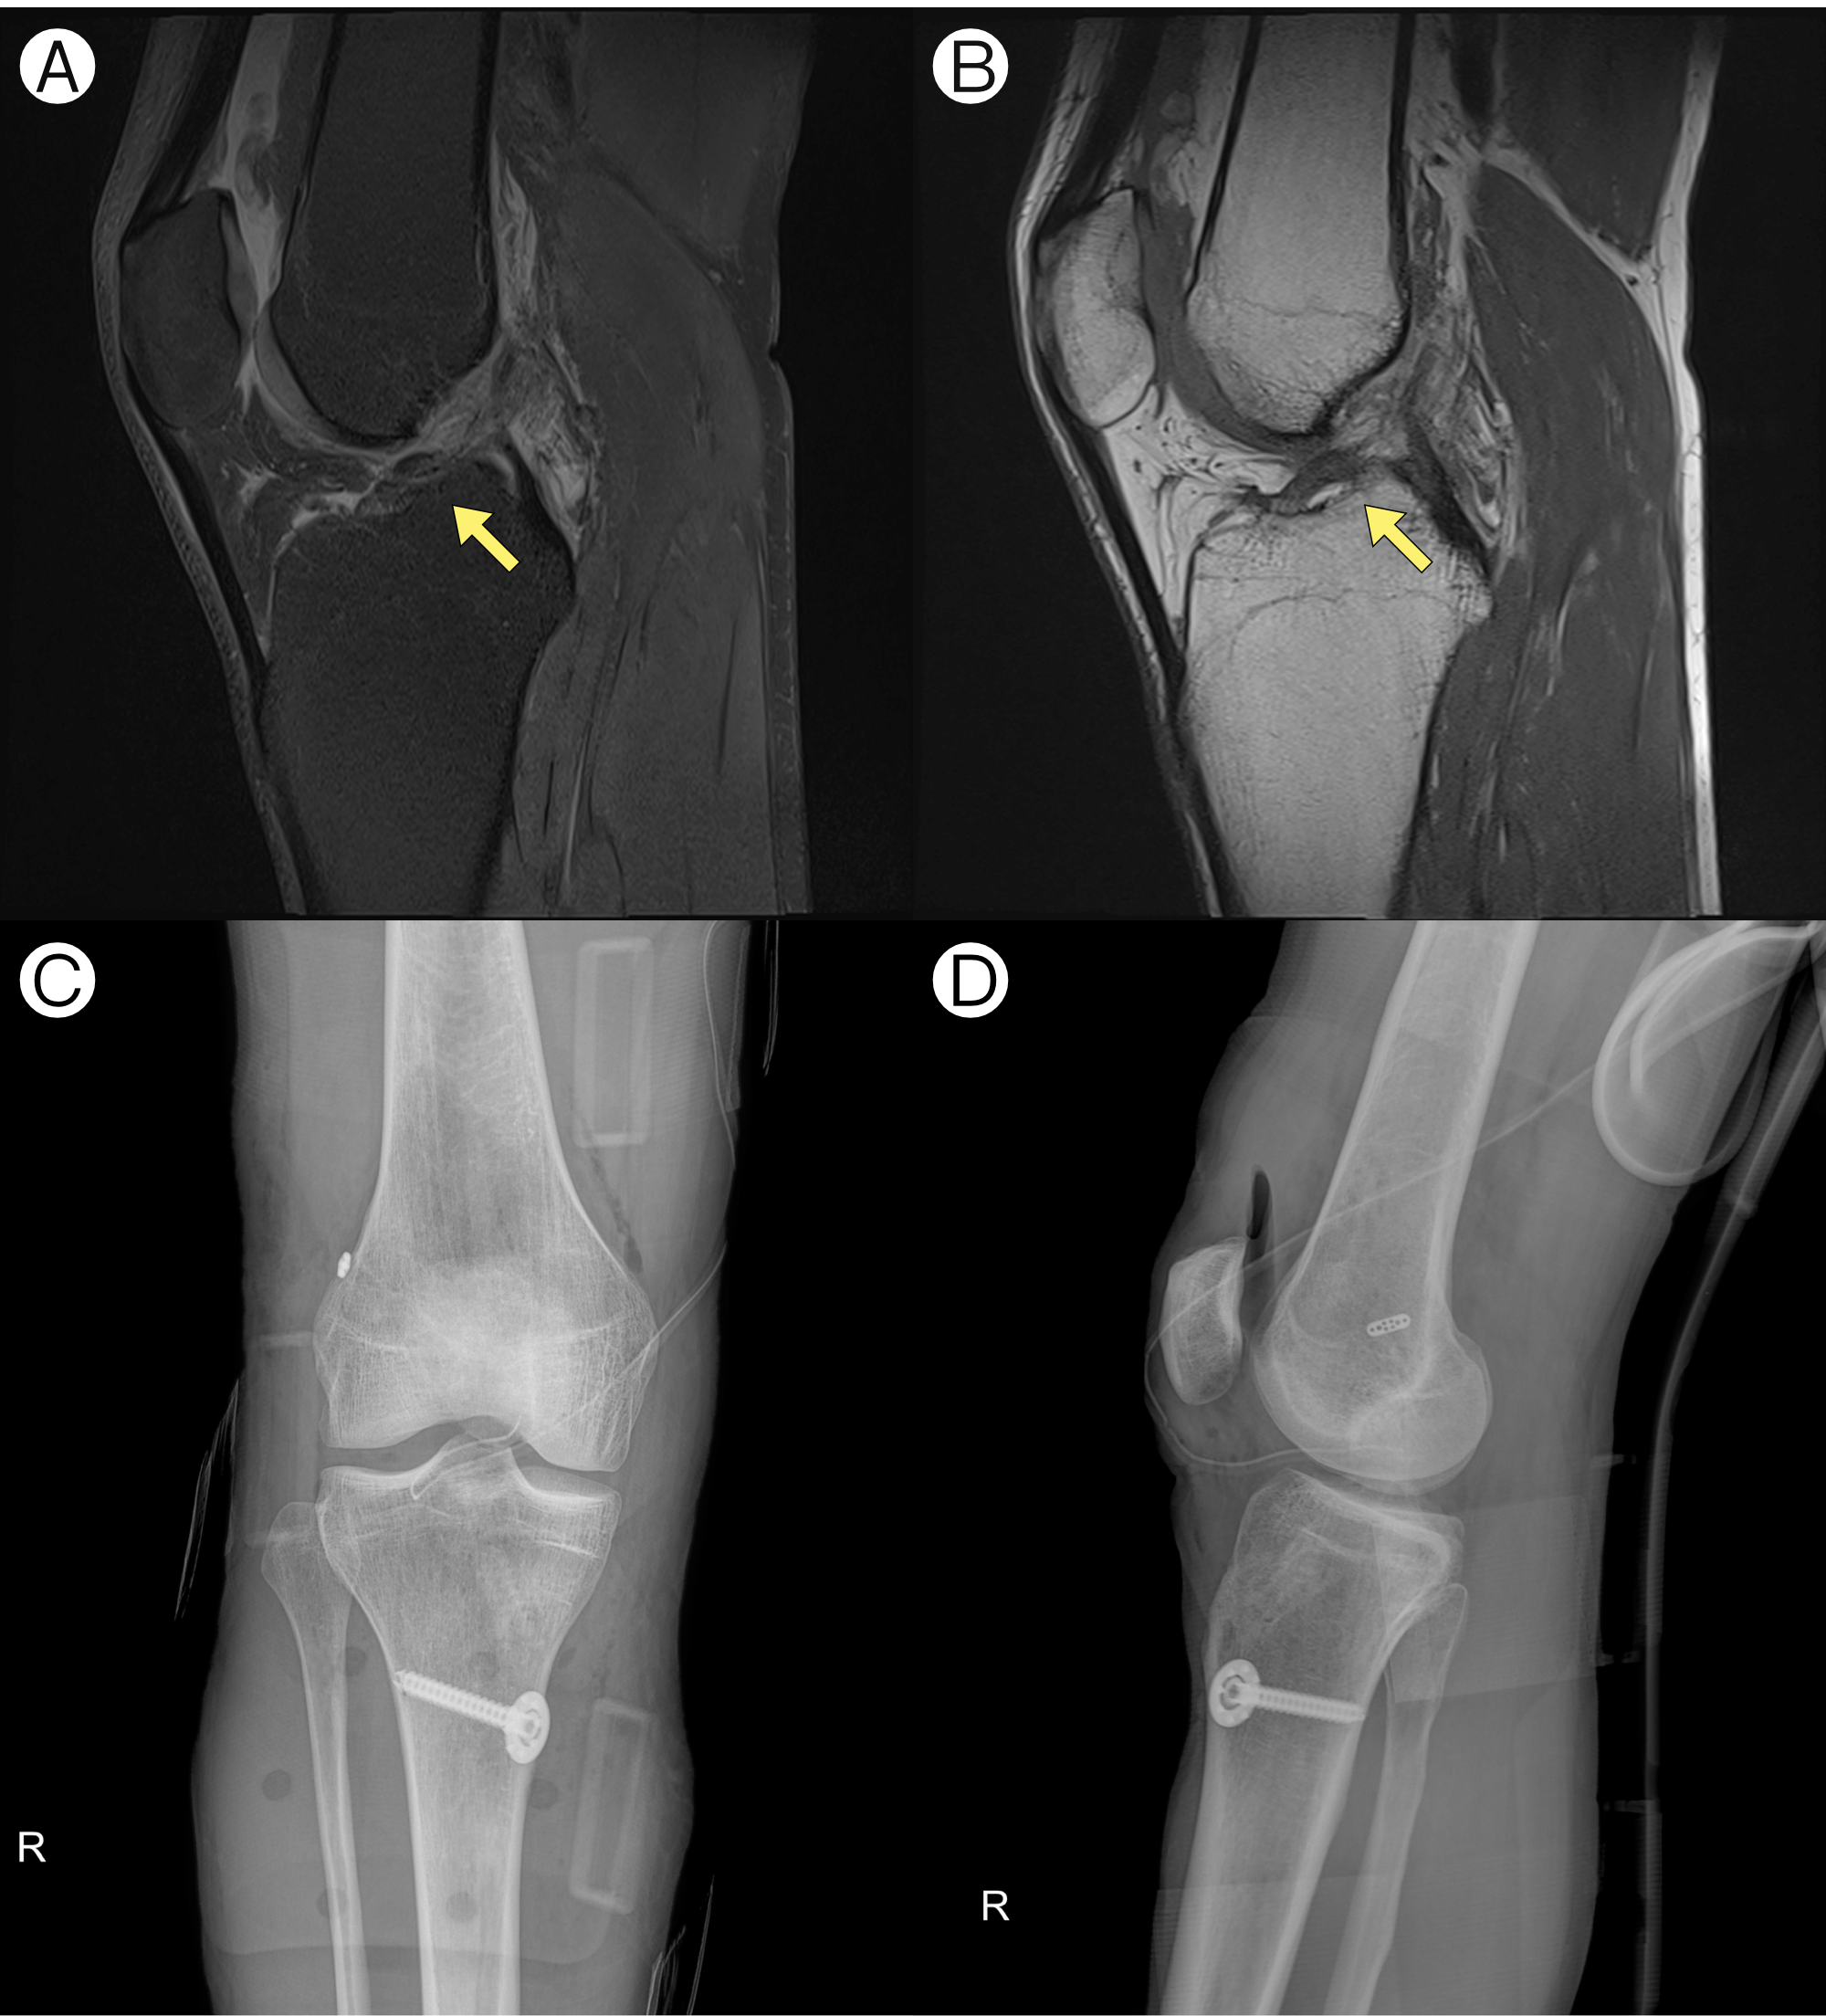

(A) Sagittal Proton Density-weighted Fat-Suppressed and (B) Sagittal T1 MRI images of a patient diagnosed with a right anterior cruciate ligament (ACL) tear; (C) Antero-Posterior and (D) Lateral X-ray images after ACL reconstruction surgery

Treatment 2: Acute ACL Tear (Post-Op Rehab)

On day 71, the patient suffered a complete (Grade 3) tear of his right ACL during judo practice. He asked, "I think there is no holistic way to rejuvenate a big ligament that is completely torn. Do you agree?"

We explained that while surgery is standard for a complete tear, "KM treatment is highly effective for post-surgical recovery and rehabilitation."

He returned to our clinic after his surgery. We used acupuncture and Hanyak to accelerate his recovery, which allowed him to minimize the use of opioid painkillers (like Tramadol). He was able to ride a bike again in just 4 months.